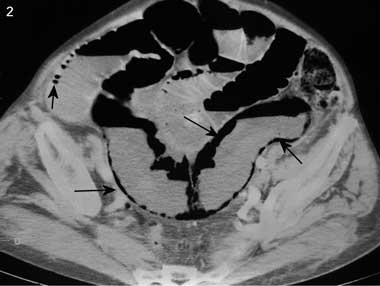

A 90-year-old woman was admitted with acute vomiting for the previous 24 hours and acute, diffuse, intense abdominal pain. Her medical history included atrial fibrillation and hysterectomy. Clinical examination revealed a generally distended, tender, tympanic and silent abdomen. Blood pressure was 98/54 mmHg; her pulse was irregular at 67 beats per minute. A plain x-ray of the abdomen revealed bowel distension without air–fluid levels. A computed tomography scan of the abdomen showed the presence of gas in the portal venous system (Box 1) and the intestinal wall (Box 2). At laparotomy, 142 cm of necrotic ileum was removed. The postoperative course was uneventful, and the patient was discharged 1 month later.

The precise mechanism for formation of gas in the portal venous system is uncertain.1 The primary factors that favour this development are intestinal wall alterations, bowel distension and intra-abdominal sepsis.1 In many cases, two or three of these circumstances may coexist. In 15% of cases, the cause of air in the portal venous system remains unknown.1 Several conditions, such as perforated ulcer, interventional procedures, trauma, and infectious or inflammatory abdominal diseases, but most commonly intestinal ischaemia (as in our patient), can cause alterations of the gastric and bowel wall, permitting the passage of intraluminal gas into the portal venous system.1-3 Gas from the intestinal lumen passes through the intestinal wall and travels via the small mesenteric veins and the superior or inferior mesenteric vein to the portal venous system. Further, the presence of gas simultaneously in the portal venous system and intestinal wall seems to be specific to intestinal ischemia.4